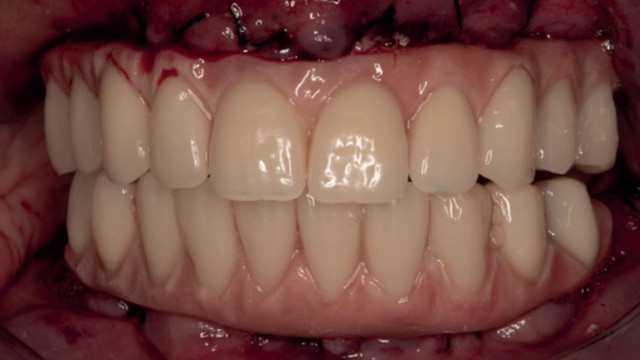

Visione intraorale delle protesi definitive consegnate alla paziente. È possibile apprezzare l’emergenza protesica che oltre a consentire un’ottima gestione del cantilever distale permette anche, grazie all’utilizzo di multi-unit abutment ed al corretto posizionamento implantare, un ridotto ingombro protesico.